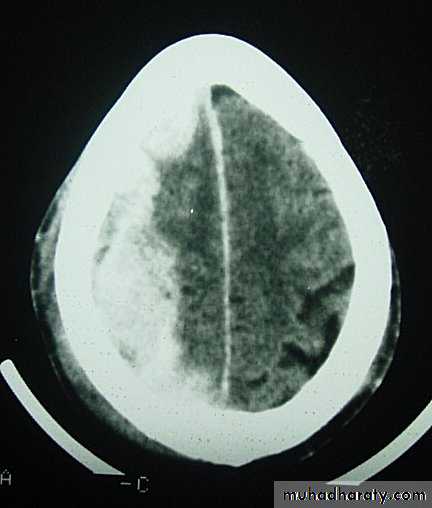

c. Intracerebral Haematoma

This is the least common of traumatic haematoma.

They are due to areas of traumatic contusion coalescing into a contusional haematoma.

Disrupted cerebral tissue release thromboplastins that potentiate haemorrhage.

CT scan: appear as hyperdence lesions with associated mass effect and midline shift.

Large intracerebral haematomas should be evacuated unless the patient’s neurological state is improving.

Small inracerebral haematomas may not require removal, but be aware that they can expand.